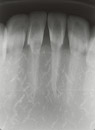

- Jaw model allows the mastering of bisecting techniques

- Jaw model is X-Ray compatible

- Acquire basic X-Ray techniques such as film angle and projection angle for each area